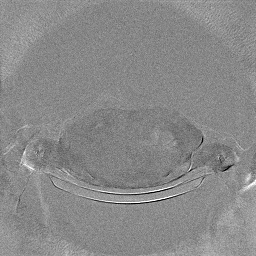

The experimental results on clinical head data are shown in Fig. 4. The reference images were reconstructed using the fast iterative shrinkage-thresholding algorithm (FISTA) with total variation regularization from non-truncated projection data. In the WCE reconstructions (Fig. 4(b)), severe truncation prevents accurate recovery of anatomical structures outside the FOV. Despite being trained solely on simulated data with a domain gap, all deep learning models can restore a substantial portion of the missing anatomy. Among them, the diffusion-based methods recover soft-tissue boundaries more faithfully than the conventional deep learning approach FBPConvNet, highlighting their stronger image generation capability. However, cDDPM reconstructions exhibit more noticeable noise than those from other methods, consistent with the simulated data results. The patchDiffusion model introduces artifacts within the FOV, likely due to its patch-wise processing strategy. While I2SB shares the same limitations as other diffusion models in perfectly restoring soft-tissue detail, it produces fewer residual noise patterns and fewer artifacts within the FOV boundaries. Overall, Fig. 4 demonstrates the strong efficacy of I2SB in reconstructing real CBCT data.